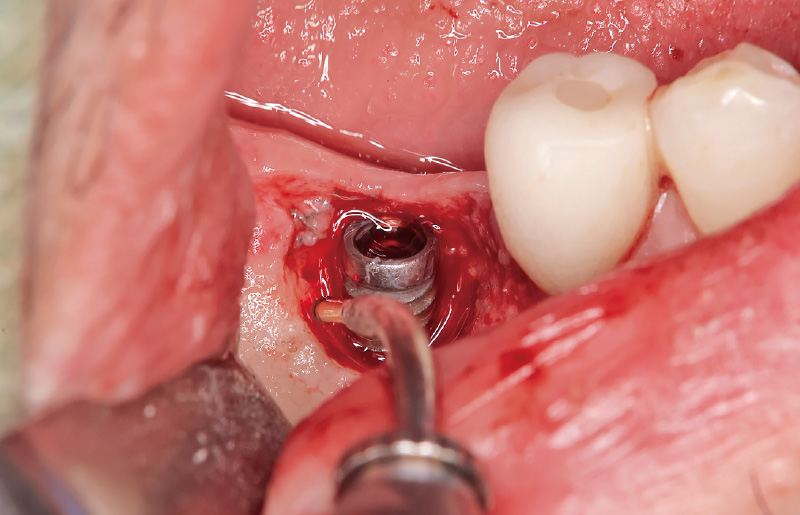

図2 全層弁剥離を行う。頰側に骨欠損を認める。 -

図3 インプラント部の感染性肉芽組織に対しては、「アドベール SH」の「不良肉芽除去」モードを使用し、インプラント体には非接触で損傷を与えることなく、また骨に熱損傷を起こすことなく、効率的に感染組織を除去した。 -

![[写真] インプラント体に非接触でデブライドメントを行った](/academic/dentalmagazine/wp-content/uploads/sites/2/2026/04//196-2_photo04.jpg)

図4 「歯石除去」モードを用い、インプラント体に非接触でデブライドメントを行った。マイクロスコープ下の拡大視野において、一層のインプラント表面を慎重に削り取るイメージで処置を行うことが重要であり、拡大視野による精密操作が治療の成否を左右する。 -